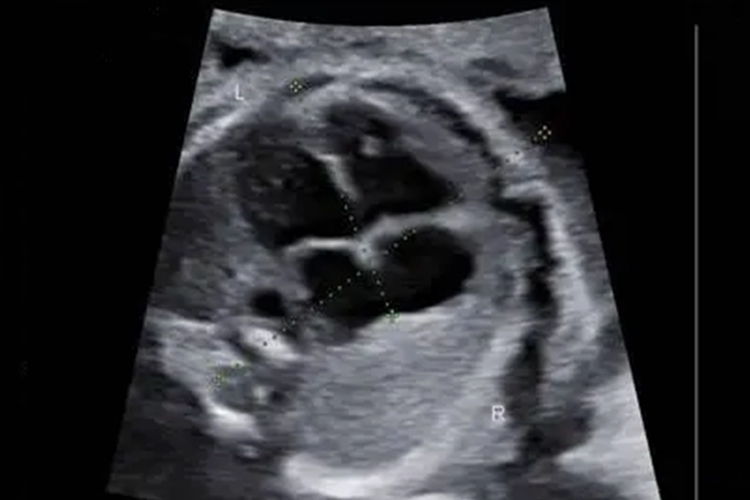

大排畸是在妊娠20-24周通过超声检查,判断胎儿是否存在脊柱椎弓间距增宽、软腭裂、心脏增宽等发育畸形情况。

大排畸通常在妊娠20-24周时进行的胎儿系统超声检查,筛查胎儿结构畸形。正常情况下胎儿心、脑、肾、膀胱、胃、上唇、四肢骨、脊柱、腹壁等均正常。当出现侧脑室增宽、脊柱椎弓间距增宽、软腭裂、双肾增大、心脏增宽、裂腹畸形伴肠管外翻等异常情况时,多提示胎儿发育异常。